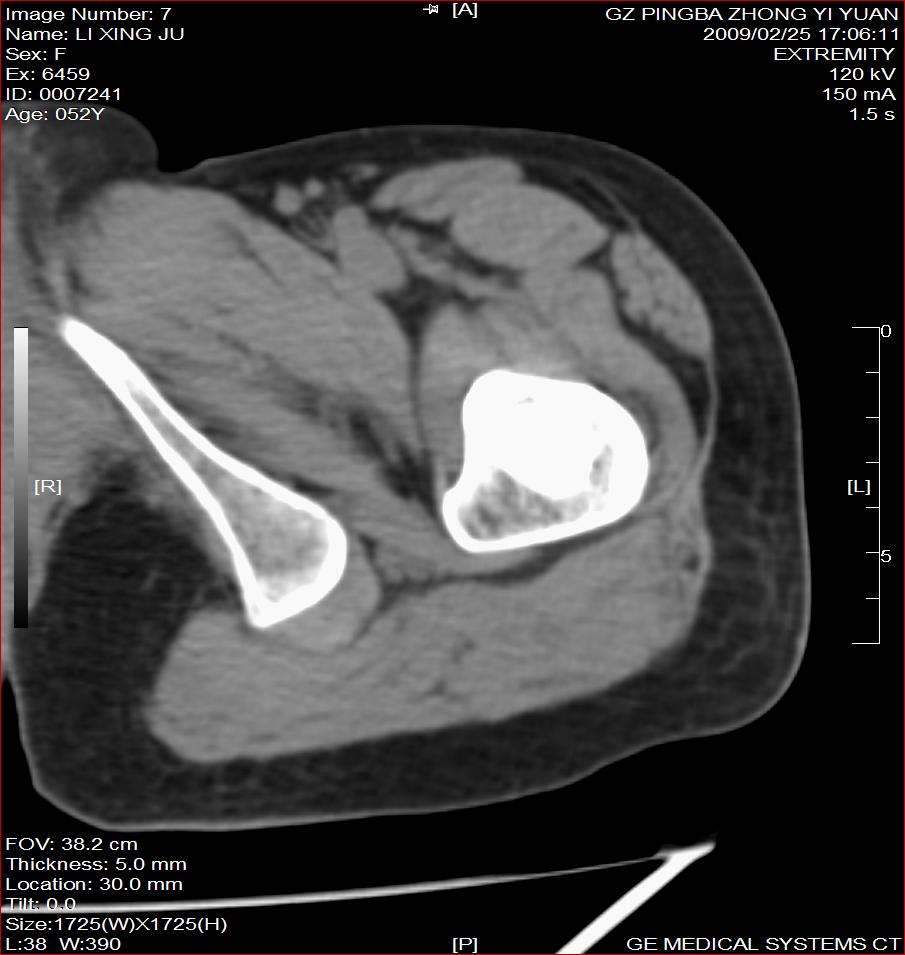

标题: CT18521:左大腿疼痛不适1+月 [打印本页]

标题: CT18521:左大腿疼痛不适1+月

考虑-----股骨骨化性纤维瘤可能性大,不除外---局限性骨纤

考虑:左股骨骨化性纤维瘤

考虑:骨纤或骨梗可能性大

考虑 左股骨骨化性纤维瘤。

骨梗塞

考虑骨化性纤维瘤可能性大